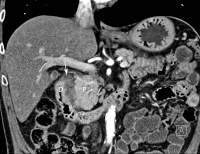

Pankreas - Adenokarzinom

Abbildung 9: Adenokarzinom des Pankreas. Die 3D-Rekonstruktion der MDCT zeigt den vom Proc. uncinatus (Pfeil) des Pankreas (P) ausgehenden Tumor, der die A. mes. sup. umwächst (Stadium T4). Es finden sich multiple Lebermetastasen (Stadium M1).

Keywords: AdenokarzinomGastroenterologieHepatologieMDCTPankreas